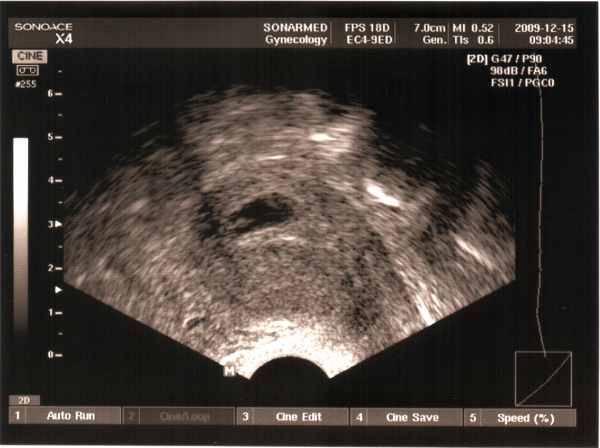

És már szépen látszik a babó